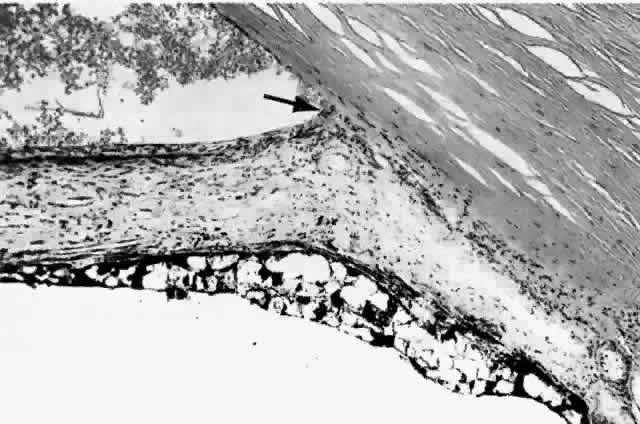

Histologically the new vessels are located anterior to the anterior border layer of the iris (Fig. 3, Color Fig. B). They are thin-walled, unlike the normal thick-walled iris stromal vessels. New vessels may be located only at the pupillary margin and in the angle at the iris root, corroborating the clinical finding.18

Fig. 3. Neovascularization glaucoma. Rubeosis iridis tends to bleed and lead to hyphema; the condition has incorrectly been called hemorrhagic glaucoma. The hemorrhage is not responsible for the glaucoma, but the rubeosis iridis and peripheral anterior synechias (arrow) are. Note the lacy vacuolization of the iris pigment epithelium. (H&E, × 75)